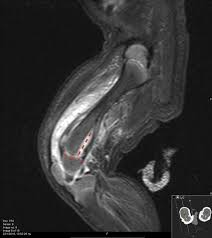

Magnetic Resonance Imaging At 7.0 T For Evaluation Of Early Lesions Of Epiphyseal  Plate And Epiphyseal End In A Rat Model Of Kashin-Beck Disease | Bmc  Musculoskeletal Disorders | Full Text